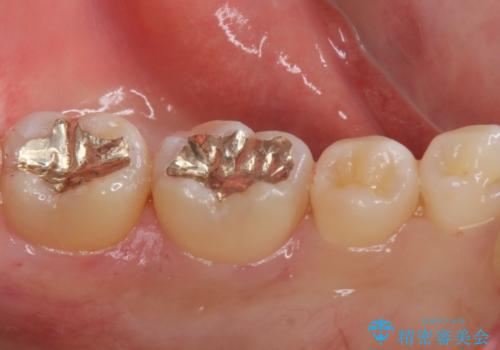

セラミック、ゴールドの詰め物のご案内をしたところゴールドを希望されたのでゴールドインレーで治療を行いました。

- ゴールドインレー 9.9万円費用は治療当時の料金となります

ゴールドの詰め物は虫歯の再発のリスクが低い材料になります。